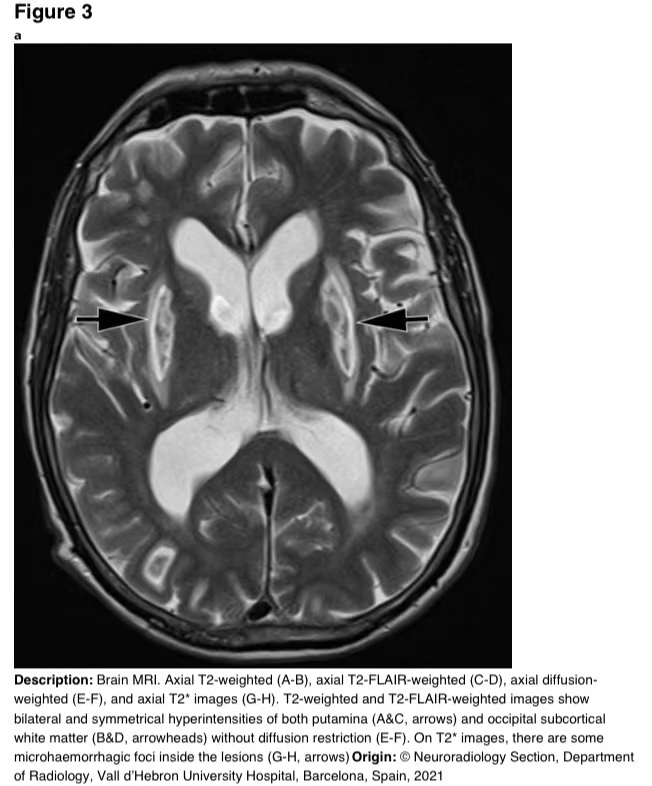

在16天的随访中,脑部MRI显示壳核和枕下皮质下白质上对称的T2/FLAIR高信号。T2图像显示病变内有微出血(图3)。

图3 a-h 脑部核磁共振成像。轴向T2加权(A-B)、轴向T2 FLAIR加权(C-D)、轴向弥散加权(E-F)和轴向T2图像(G-H)。T2加权和T2 FLAIR加权图像显示双侧和对称的壳核高信号(A和C,箭头)和枕下皮质下白质高信号(B和D,箭头),无弥散限制(E-F)。在T2图像上,病变内有一些微出血病灶(G-H,箭头)。